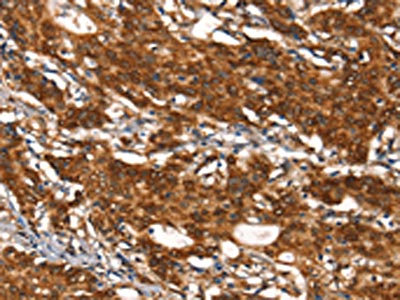

The image on the left is immunohistochemistry of paraffin-embedded Human gastic cancer tissue using CSB-PA051152(CYP2D6 Antibody) at dilution 1/30, on the right is treated with synthetic peptide. (Original magnification: ×200)

The image on the left is immunohistochemistry of paraffin-embedded Human thyroid cancer tissue using CSB-PA051152(CYP2D6 Antibody) at dilution 1/30, on the right is treated with synthetic peptide. (Original magnification: ×200)